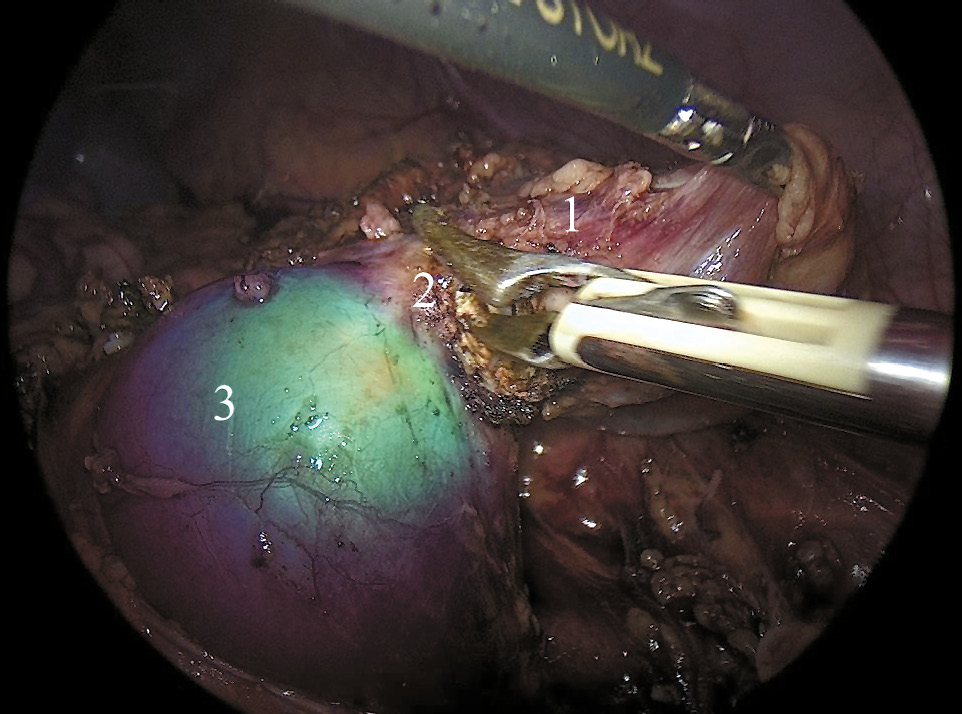

Монохромный режим может отображать сигнал ICG-NIRF в монохромном белом цвете на черном фоне для лучшей дифференциации флюоресцирующих тканей — правая половина ПОП окрасилась насыщенным белым цветом, поражённый левый сегмент не окрасился (рис. 3).

Рис. 3. Визуализация подковообразной почки в режиме монохромного изображения: 1 — левая половина подковообразной почки, 2 — перешеек подковообразной почки, 3 — правая половина подковообразной почки.

Режим картирования интенсивности сигнала ICG-NIRF предоставляет хирургу цветовую шкалу в наложенном изображении — здоровая правая половина ПОП окрасилась в насыщенные зелено-синие оттенки, левый сегмент не окрасился (рис. 4).

Рис. 4. Визуализация подковообразной почки в режиме цветного картирования: 1 — левая половина подковообразной почки, 2 — перешеек подковообразной почки, 3 — правая половина подковообразной почки.

Затем мы пересекли перешеек почки на границе свечения, используя технологию электролигирования BiClamp компании ERBE (рис. 5). Мочеточник удалённой части выделяли как можно дистальнее и герметизировали на уровне мочевого пузыря, используя клипсы Hem-o-Lok.

Рис. 5. Лапароскопическая резекция левой половины подковообразной почки, визуализация в режиме наложения изображения: 1 — левая половина подковообразной почки, 2 — перешеек подковообразной почки, 3 — правая половина подковообразной почки.